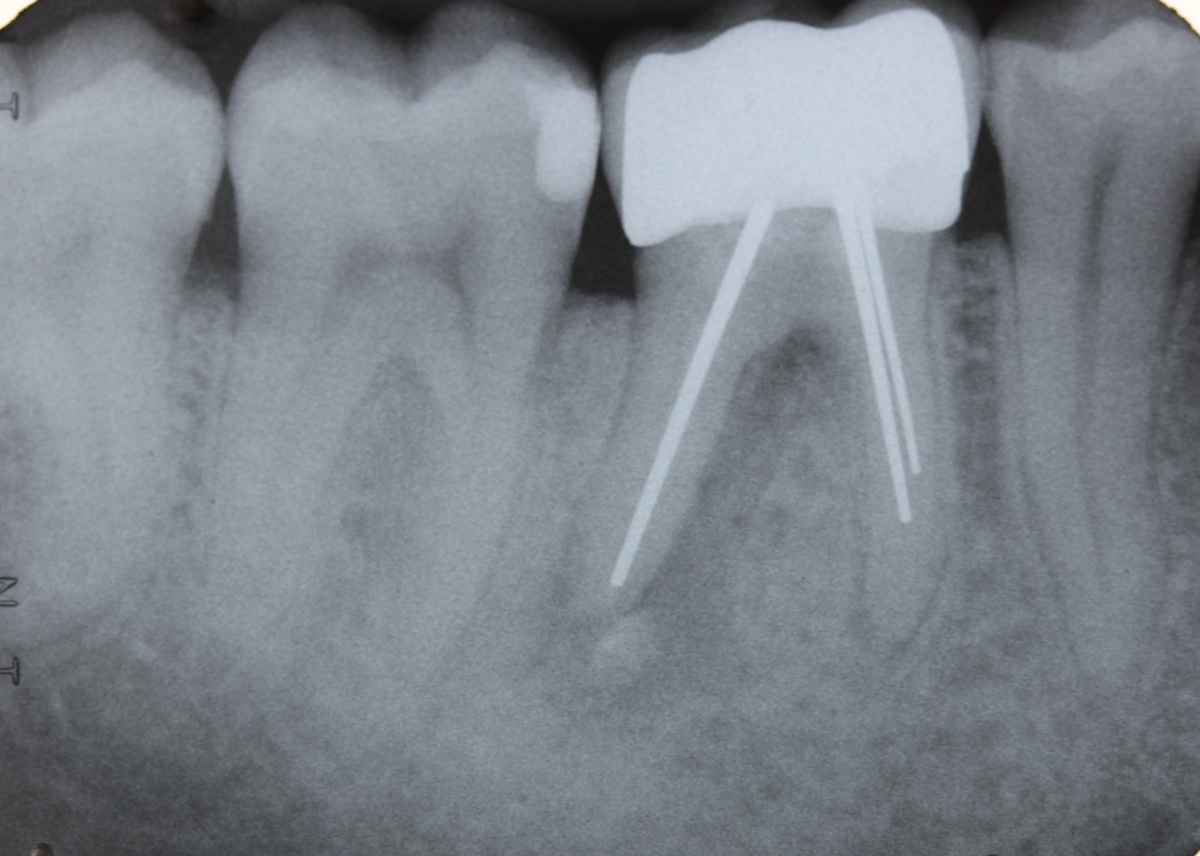

Dem Behandler kommt die Aufgabe zu, behandlungsbedingte Fehlerquellen möglichst auszuschalten. Eine solche kann die Ausdehnung der Trepanationsöffnung sein. Weitestgehend bekannt ist, dass ein gradliniger Zugang zu den Wurzelkanälen geschaffen werden sollte. Dieser technisch einfach umzusetzende Behandlungsschritt hilft den mechanischen „Stress“ durch Torsion auf die NiTi-Feilen deutlich zu verringern. Klinisch werden in nicht seltenen Fällen jedoch deutlich unterdimensionierte Trepanationsöffnungen oder persistierende Überhänge vorgefunden, welche die Belastung auf die Feilen unnötig erhöhen. Aufgrund stetig verbesserter technischer Möglichkeiten, wie beispielsweise die Anwendung hochauflösender Operationsmikroskope sowie der Ultraschalltechnologie, zieht heutzutage allerdings die Fraktur einer Feile selten die sofortige Extraktion nach sich. Sehr häufig ist die orthograde, bei ungünstiger Lage des Fragments seltener die retrograde, Entfernung möglich. Unter besonderen Voraussetzungen bei gleichzeitigem Abwägen des Risiko-/Nutzenverhältnisses ist auch das Belassen des separierten Instruments als praktikable Lösung möglich (Abb. 9 und 10).